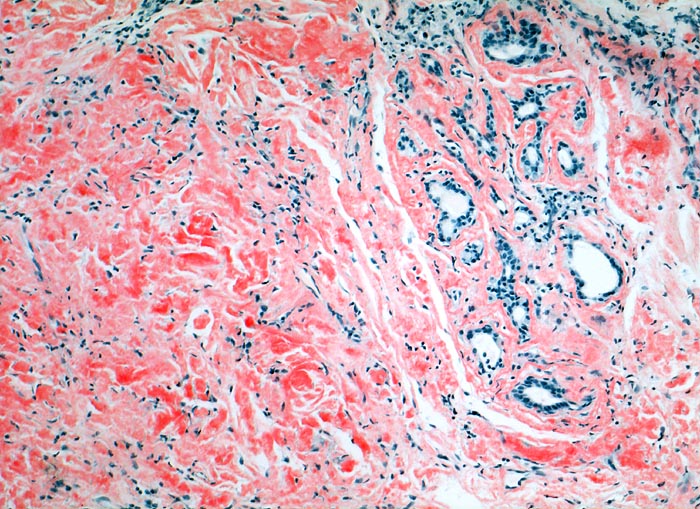

Lokalisierte Amyloidose

Larynx

Massenhaft kongorote Amyloidablagerungen im Stroma.

Immunhistochemisch AL-Amyloid

Bei der laryngealen Amyloidose handelt es sich oftmals um eine lokalisierte Erkrankung ohne Systembeteiligung. Sie kann zu heiserer Stimme oder Dyspnoe führen. Meist handelt es sich wie im vorliegenden Fall um AL-Amyloid. Nach einer Systembeteiligung sollte klinisch gesucht werden.